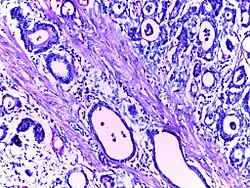

Cystic hyperplasia of endometrium | Micrograph showing cystic hyperplasia of endometrium. Cystically dialated glands are lined by proliferative type of epithelium. Stroma also resembles proliferative phase. No atypia is seen in the cells. | Category: Histopathology of hyperplasia endometrium | Cystic hyperplasia |

![]() |